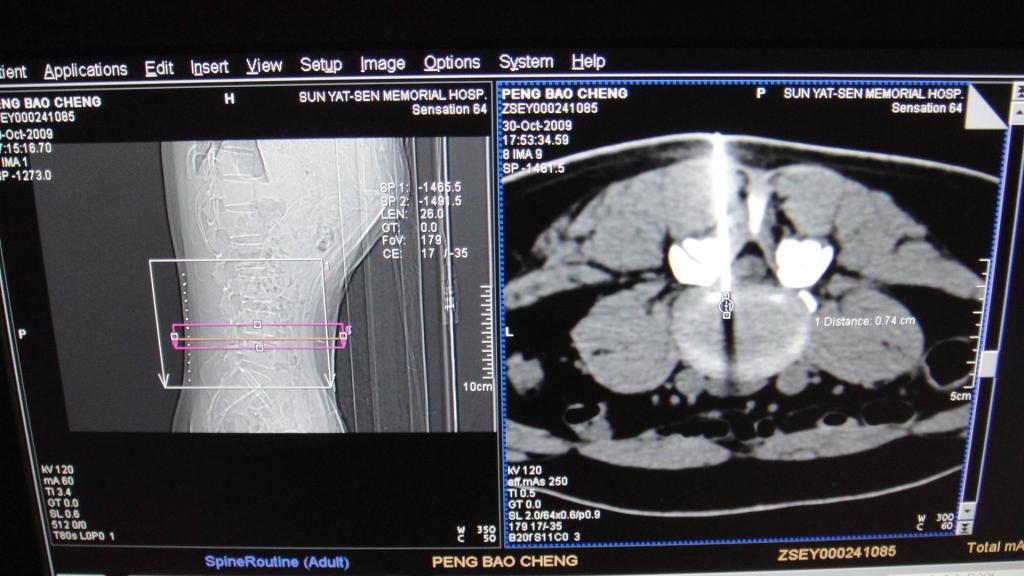

CT引导射频靶点热凝术

CT精确定位